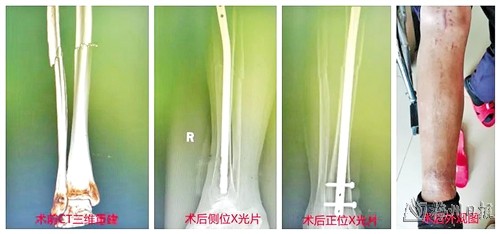

因外伤造成胫骨干骨折的患者术前术后的对比图片。(受访者供图)

近日,平远县人民医院收治了3名因外伤造成胫骨干骨折的患者,在骨科主任肖胜添的带领下,医护人员利用微创切口胫骨髓内钉技术成功完成了手术,术后,患者们恢复良好,骨折复位也达到了预期效果。